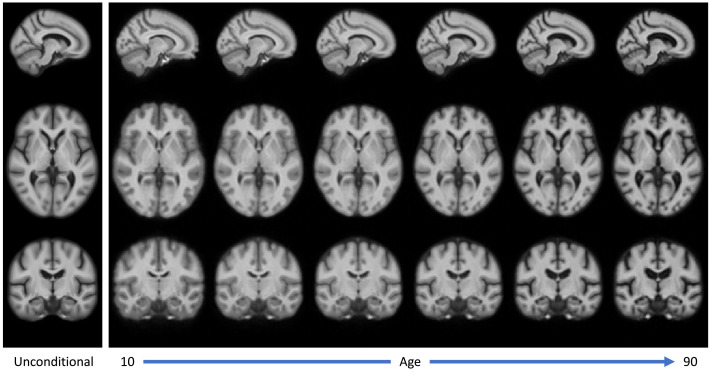

图5.通过AtlasMorph获得的强度模板。左图:无条件强度模板。右图:从我们学习到的模板函数中抽样得到的年龄从10岁到90岁的条件强度模板,从左到右。条件模板捕捉到了年龄相关的萎缩的已知迹象,如在图12中分析。

图6.通过AtlasMorph获得的标签图模板。左图:无条件标签图模板。右图:条件标签图。从我们学习到的模板函数中抽样得到的年龄从10岁到90岁的模板,从左到右。标签图的可视化是通过为每个类别分配最高概率的标签获得的。条件模板捕捉到了年龄相关的萎缩的已知迹象。